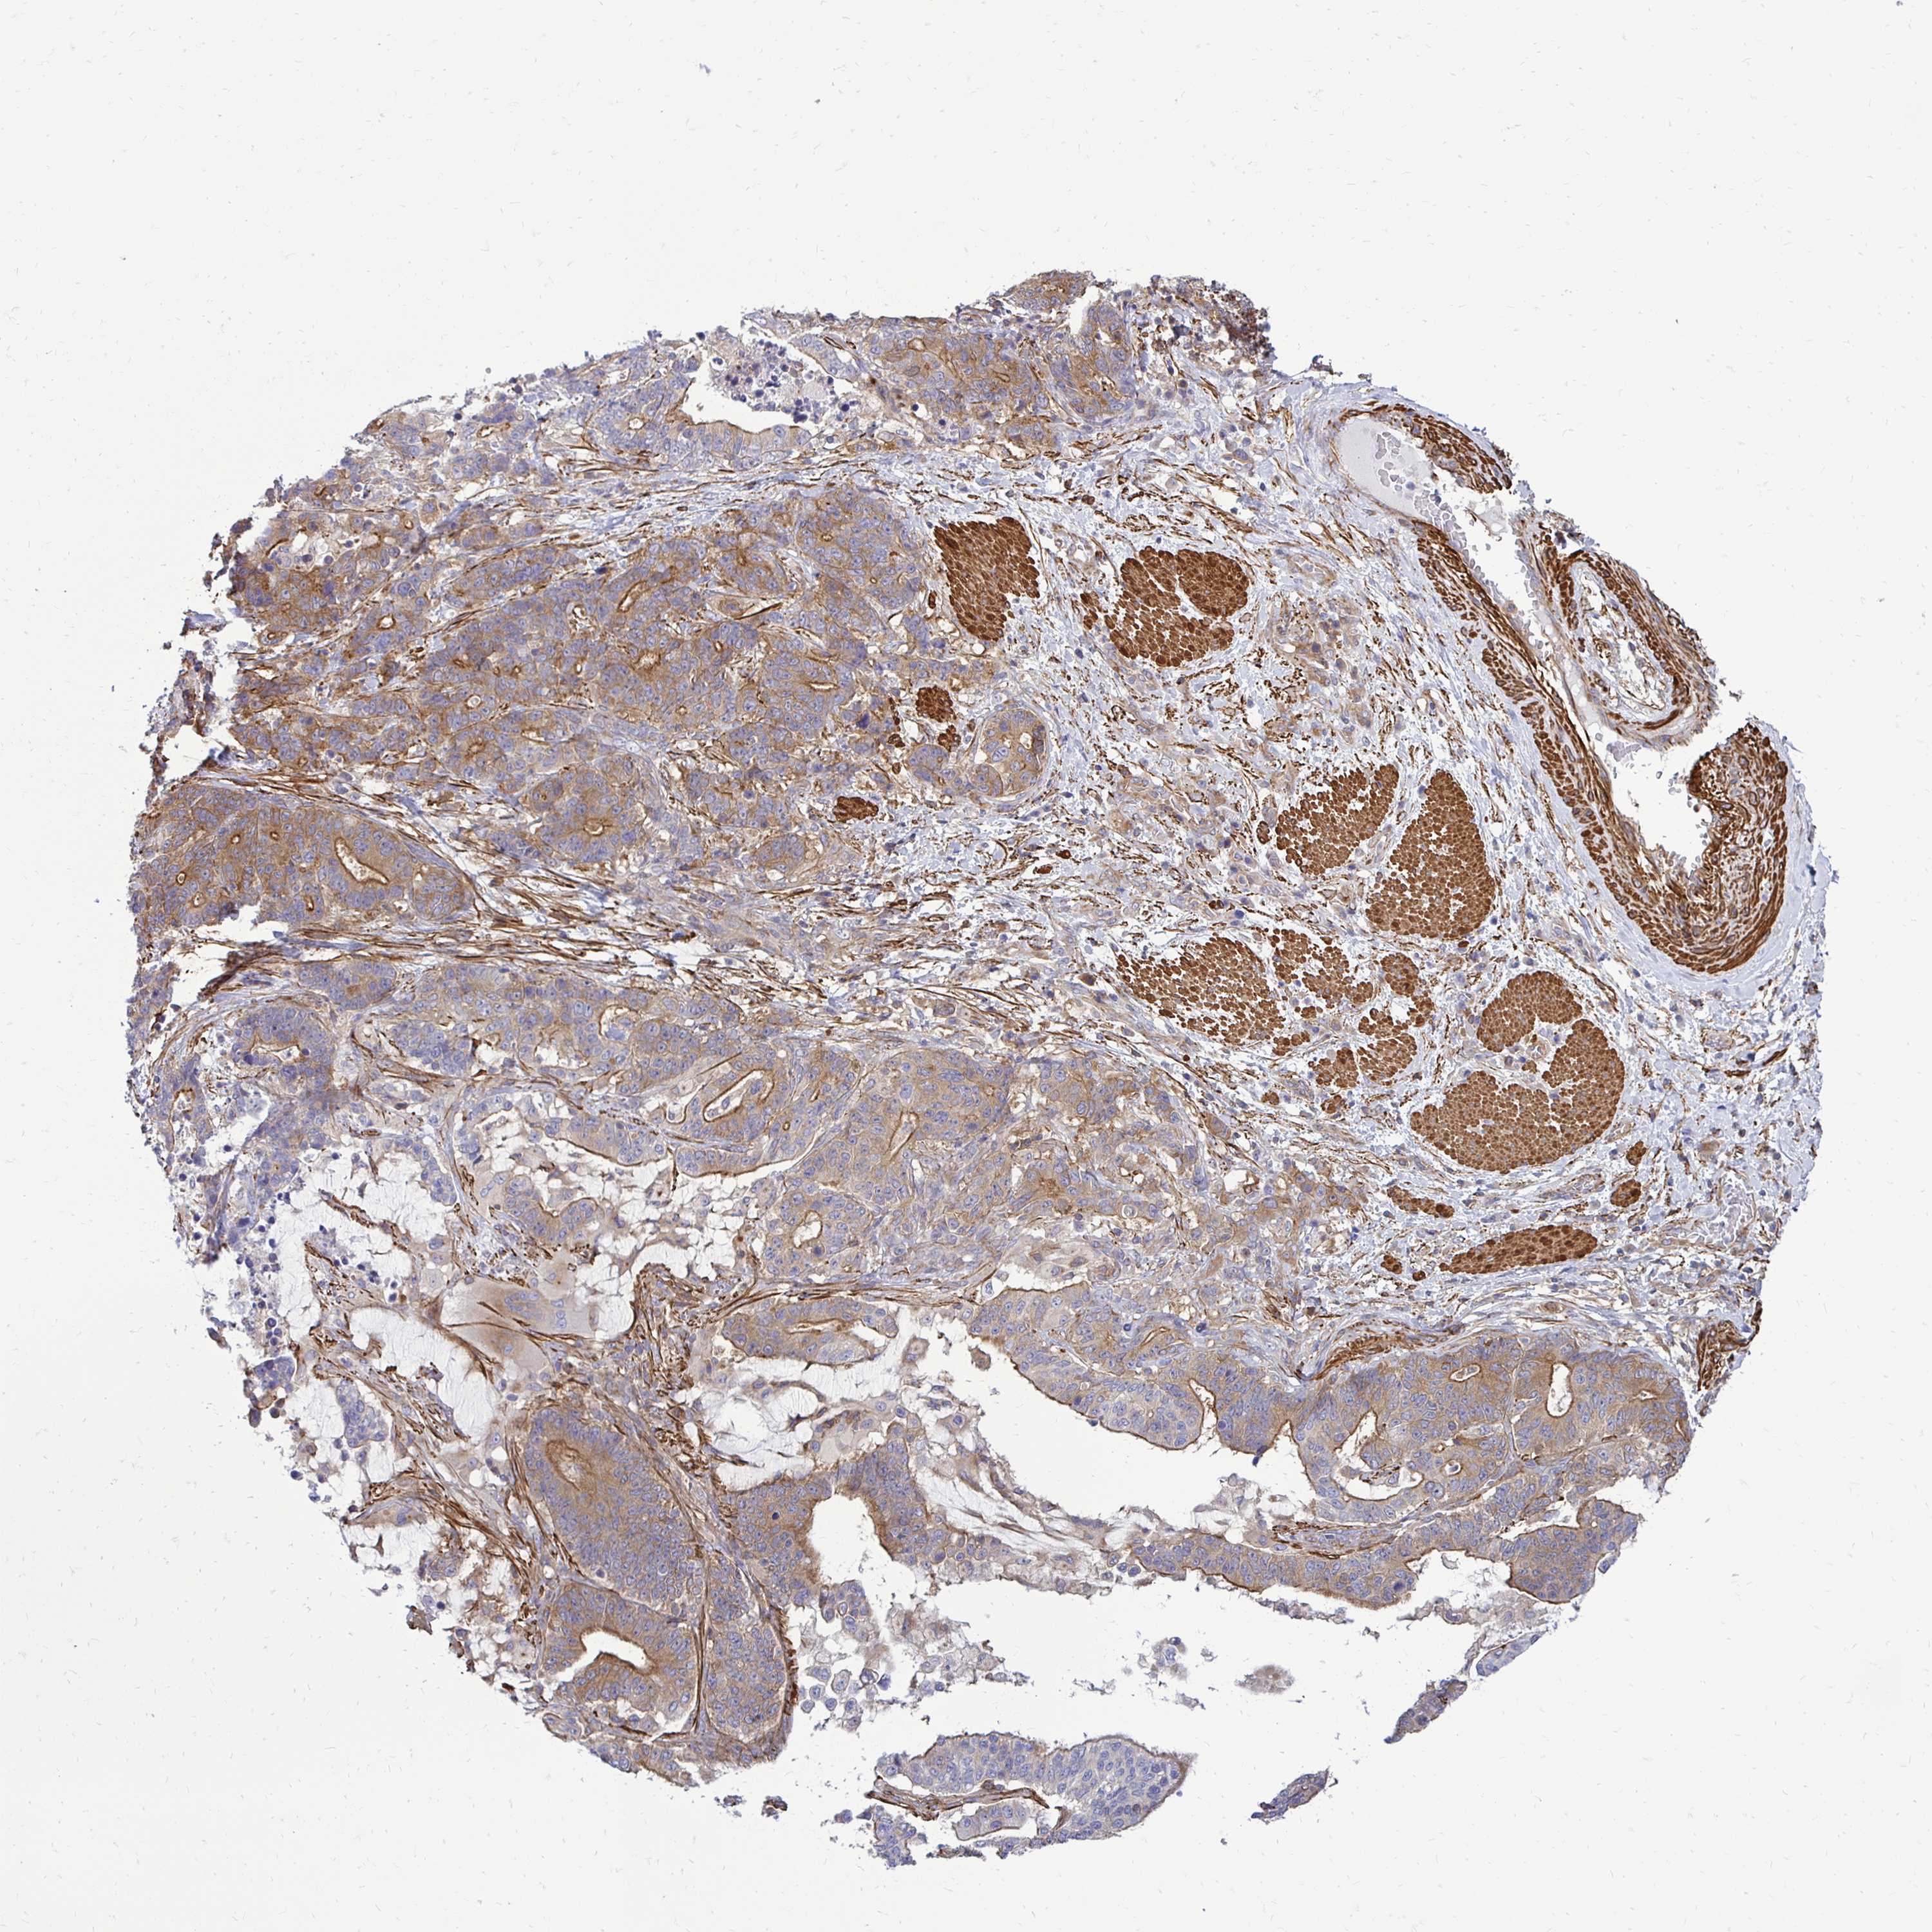

STOMACH CANCER - Protein expressioni

A mouse-over function shows sample information and annotation data. Click on an image to view it in a full screen mode. Samples can be filtered based on level of antibody staining by selecting one or several of the following categories: high, medium, low and not detected. The assay and annotation is described here.

Note that samples used for immunohistochemistry by the Human Protein Atlas do not correspond to samples in the TCGA dataset.

Antibody stainingi

Antibody staining in the annotated cell types in the current human tissue is reported as not detected, low, medium, or high, based on conventional immunohistochemistry profiling in selected tissues. This score is based on the combination of the staining intensity and fraction of stained cells.

Each image is clickable and will lead to virtual microscopy that enables deeper exploration of all samples and also displays staining intensity scores, fraction scores and subcellular localization as well as patient and tissue information for each sample.

Antibody HPA051322

Antibody CAB017111

Staining

High

Medium

Low

Not detected

Intensity

Strong

Moderate

Weak

Negative

Quantity

>75%

75%-25%

<25%

None

Location

Nuclear

Cytoplasmic/membranous

Cytoplasmic/membranous,nuclear

Adenocarcinoma, NOS

Adenocarcinoma, High grade